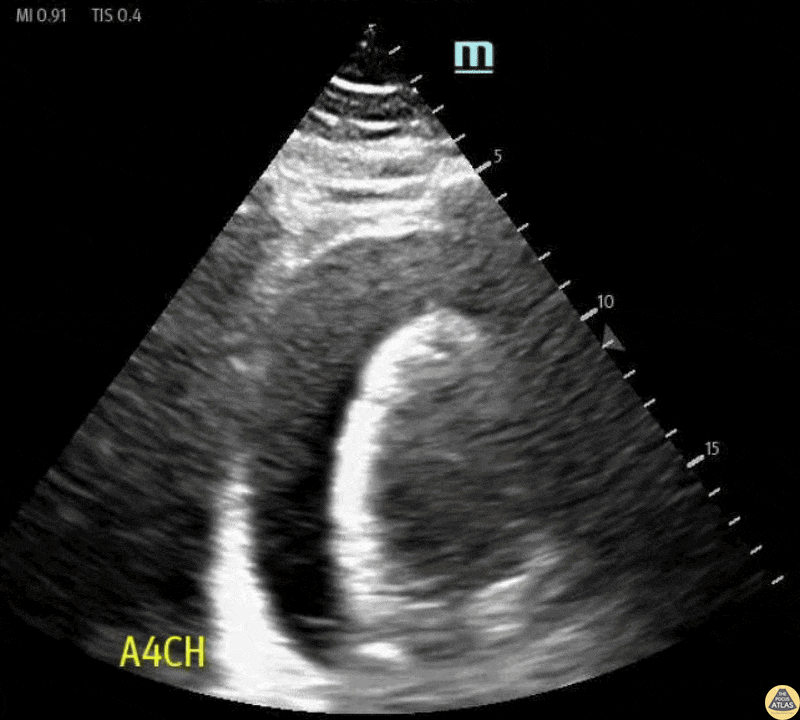

Pericardial Disease - Cardiac Tamponade in Apical 4-Chamber View

52 y/o male, with PMH of T2DM, HTN, Obstructive Sleep Apnea, and Hyperlipidemia presented to the Emergency Department with worsening SOB for 1 month. Bedside Cardiac US demonstrated large pericardial effusion. Patient was sent to the OR for an emergency pericardiocentesis with removal of 1.1 L of fluid. Contributors: Dr. Lauren Lowes, DO; Dr. Shivani Lohit, MD; Maya Eylon MS4 Central Michigan University College of Medicine, Emergency Medicine